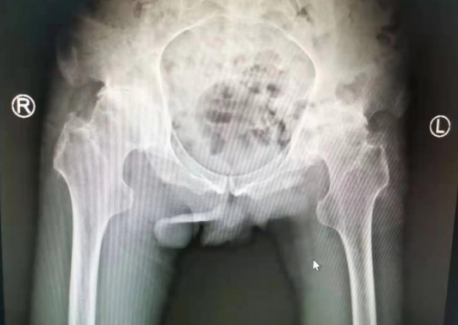

关节科蒋守海主任给吕师傅做了检查,吕师傅的左右髋关节内收外展、内外旋均不能;由于长时间坐轮椅,吕师傅的下肢肌肉已经开始萎缩,左下肢比右下肢短2厘米,摄片显示双侧骨头密度增高,双髋关节间隙狭窄,双髋臼缘及股骨近端见骨质增生,诊断为双侧股骨头无菌性坏死,强直性脊柱炎,左股骨近端陈旧性骨折。患者才32岁,如果要挽救髋部功能,必须进行髋关节置换手术。

术前